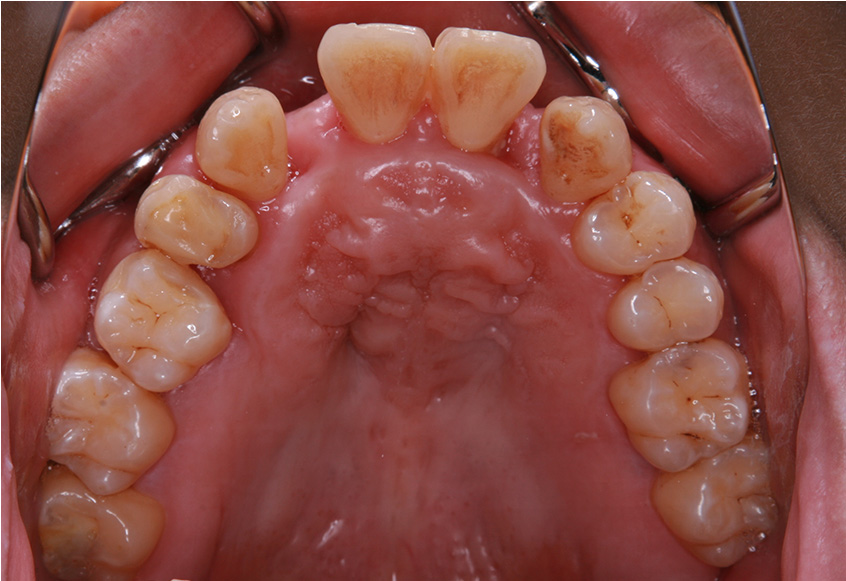

親知らずの痛みがなくなった患者さんは、昔から歯並びが気になっていることを打ち明けてくれました。特に上の歯が少し前に出ていたり、隙間があったりしている点を治したいそうです。そこで、まず上の歯並びの矯正治療を開始しました。

最初のお口の中 ワイヤー装着して治療を開始